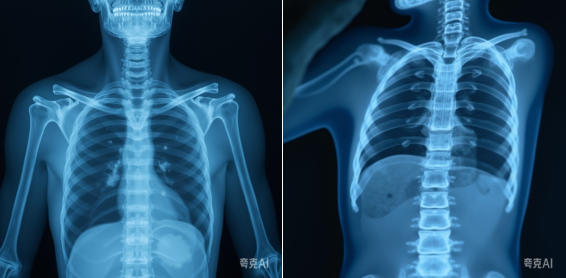

移动式数字X射线摄影设备(移动DR)作为危急时刻的“生命之眼”,在急诊和ICU等场景中发挥着不可替代的作用。然而,其辐射安全问题常引发公众担忧,而长期接触电离辐射的放射科医护人员更需科学防护。本文结合科学数据与防护实践,全面解读移动DR的安全性,并为医护人员提供系统防护策略。

一、移动DR的科学解读:辐射真相与安全边界

1. 应用场景与核心优势

移动DR专为无法转运的重症患者设计,可快速完成床旁影像检查,适用于:

· 急诊抢救:快速评估伤情。

· 无法移动的患者如重症监护(ICU)、骨科牵引患者。

其他患者应优先使用固定DR设备,以减少不必要的辐射暴露。